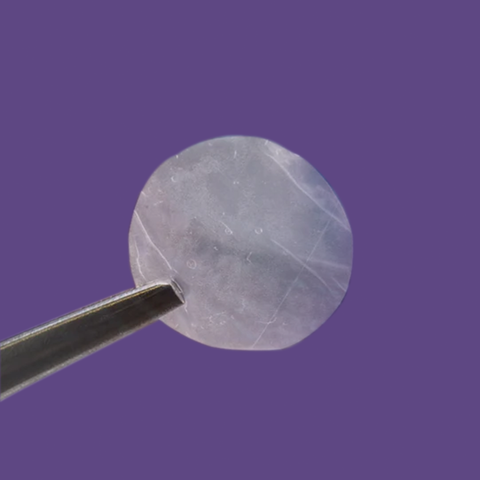

• Textured surface facilitates ease of handling and placement

• Symmetric graft allows either side to be placed in contact with ocular surface

• Can be placed in either direction (multi-directional graft)

• Has a micron thickness of 30-35 Microns

Apply either graft surface to the wound site; Symmetric design removes stromal layer/epithelial layer facing requirements

Graft may be manipulated in place and/or repositioned during surgery